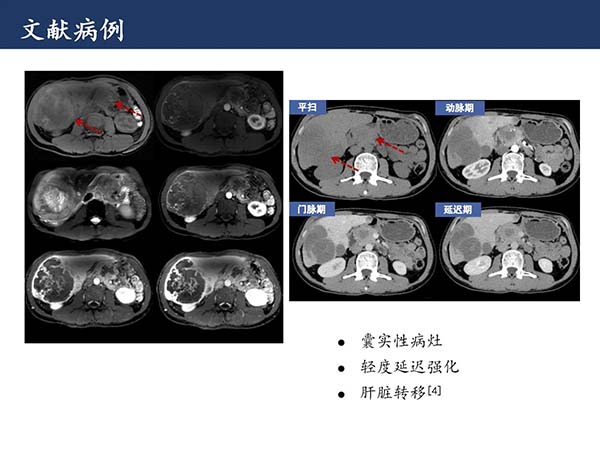

【杨柳病例】胰腺实性假乳头状瘤伴肝转移一例MRI影像诊断